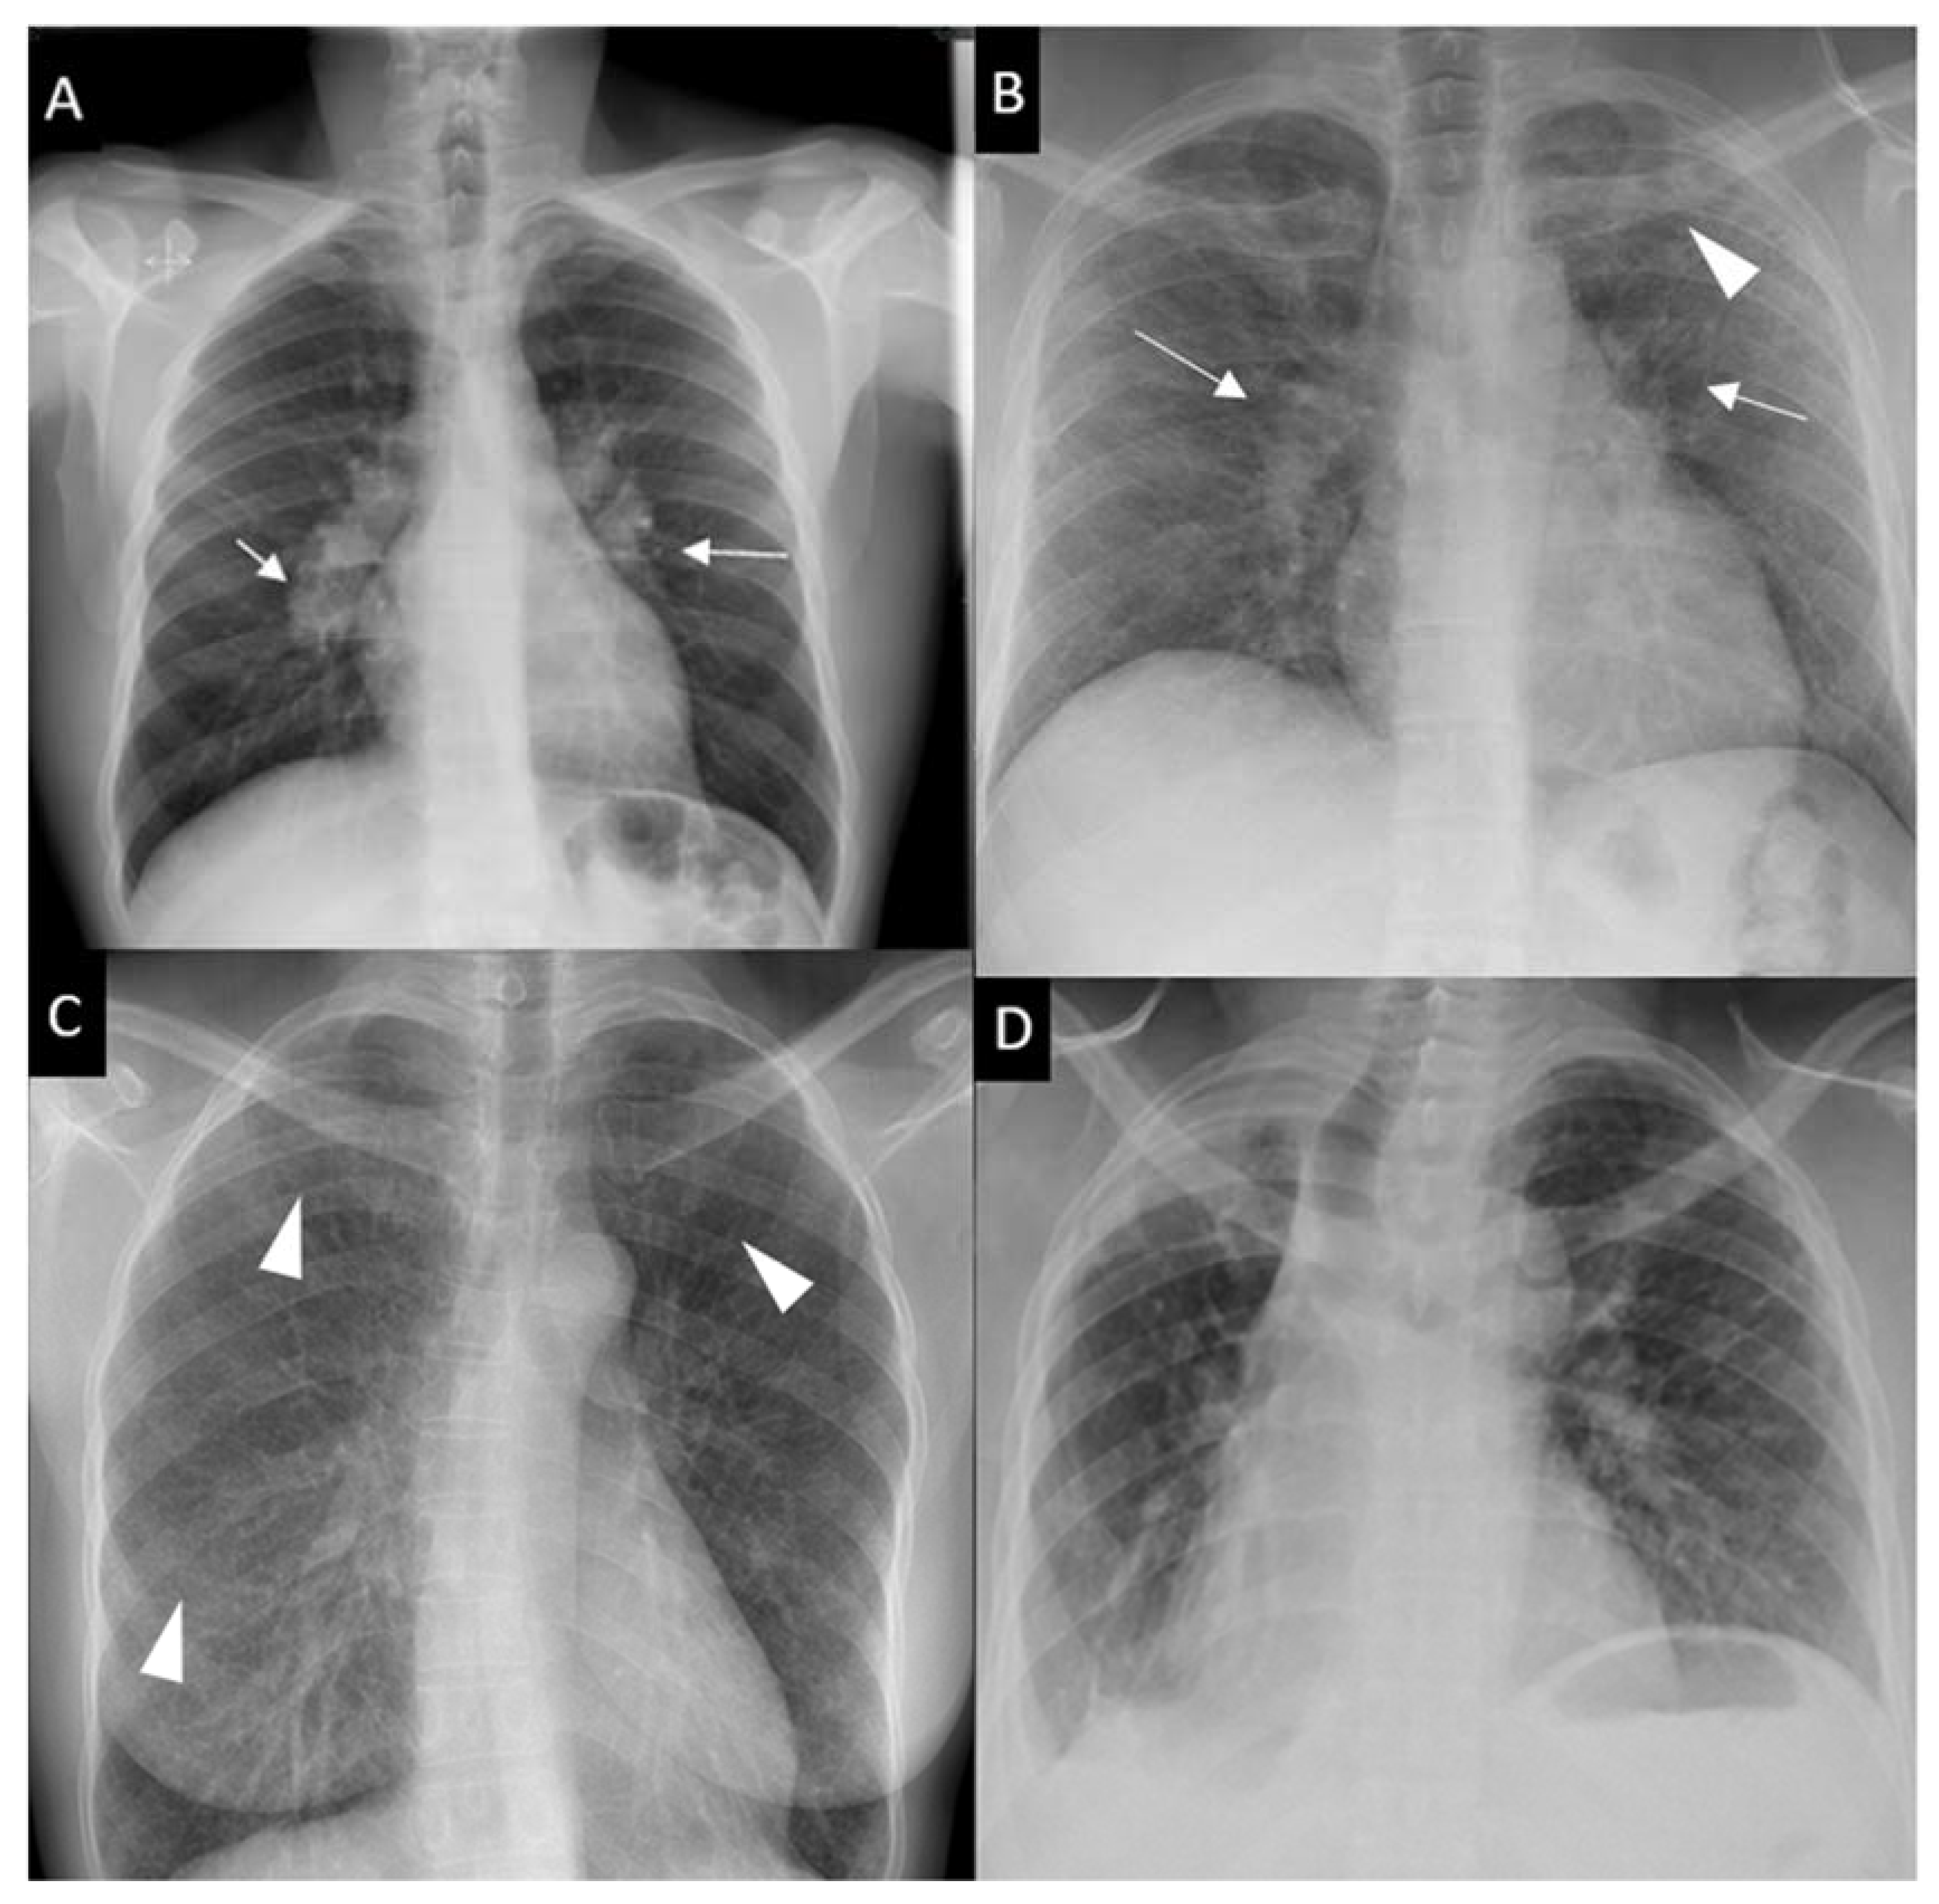

• CXR Staging (Scadding):

![CXR Sarcoidosis Stages I-IV](https://ylbwdadhbcjolwylidja.supabase.co/storage/v1/object/public/notes/L1/Internal_Medicine_Pulmonology_Interstitial_Lung_Diseases/30f05fd5-1ed8-465f-a93d-c21ac9db429c.png)